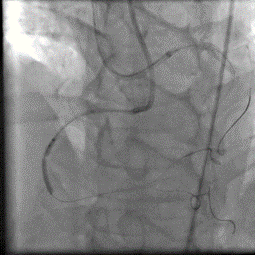

术前造影

术后造影